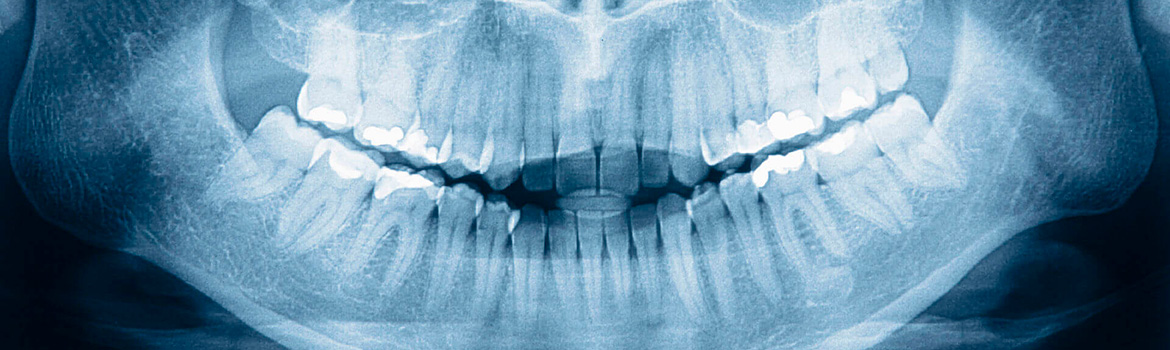

Рентгенография небного шва: Медицинские исследования и диагностика